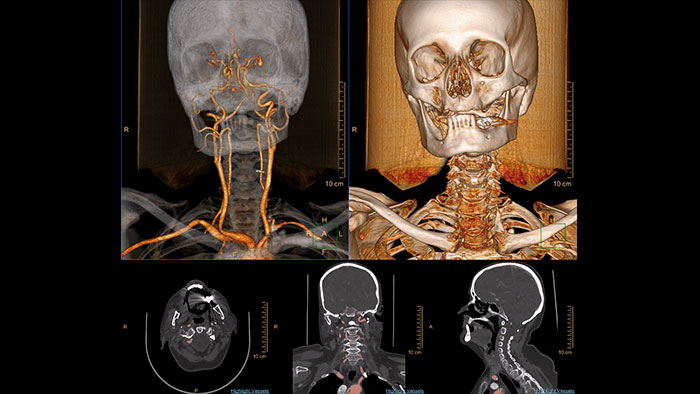

Comprehensive vascular analysis planning

Designed to examine and quantify different types of vascular lesions from CTA and MRA scans. It accommodates different modes of inspection, allows labeling different vascular lesions, and helps navigating through multiple findings. Demonstrated to reduce the post-processing time by 50% when compared to manual Head & Neck CT angiography (CTA) analysis*.

Benefits

* Ardley N et al. Efficacy of a new post processing workflow for CTA head and neck. ECR 2013 / C-1760.